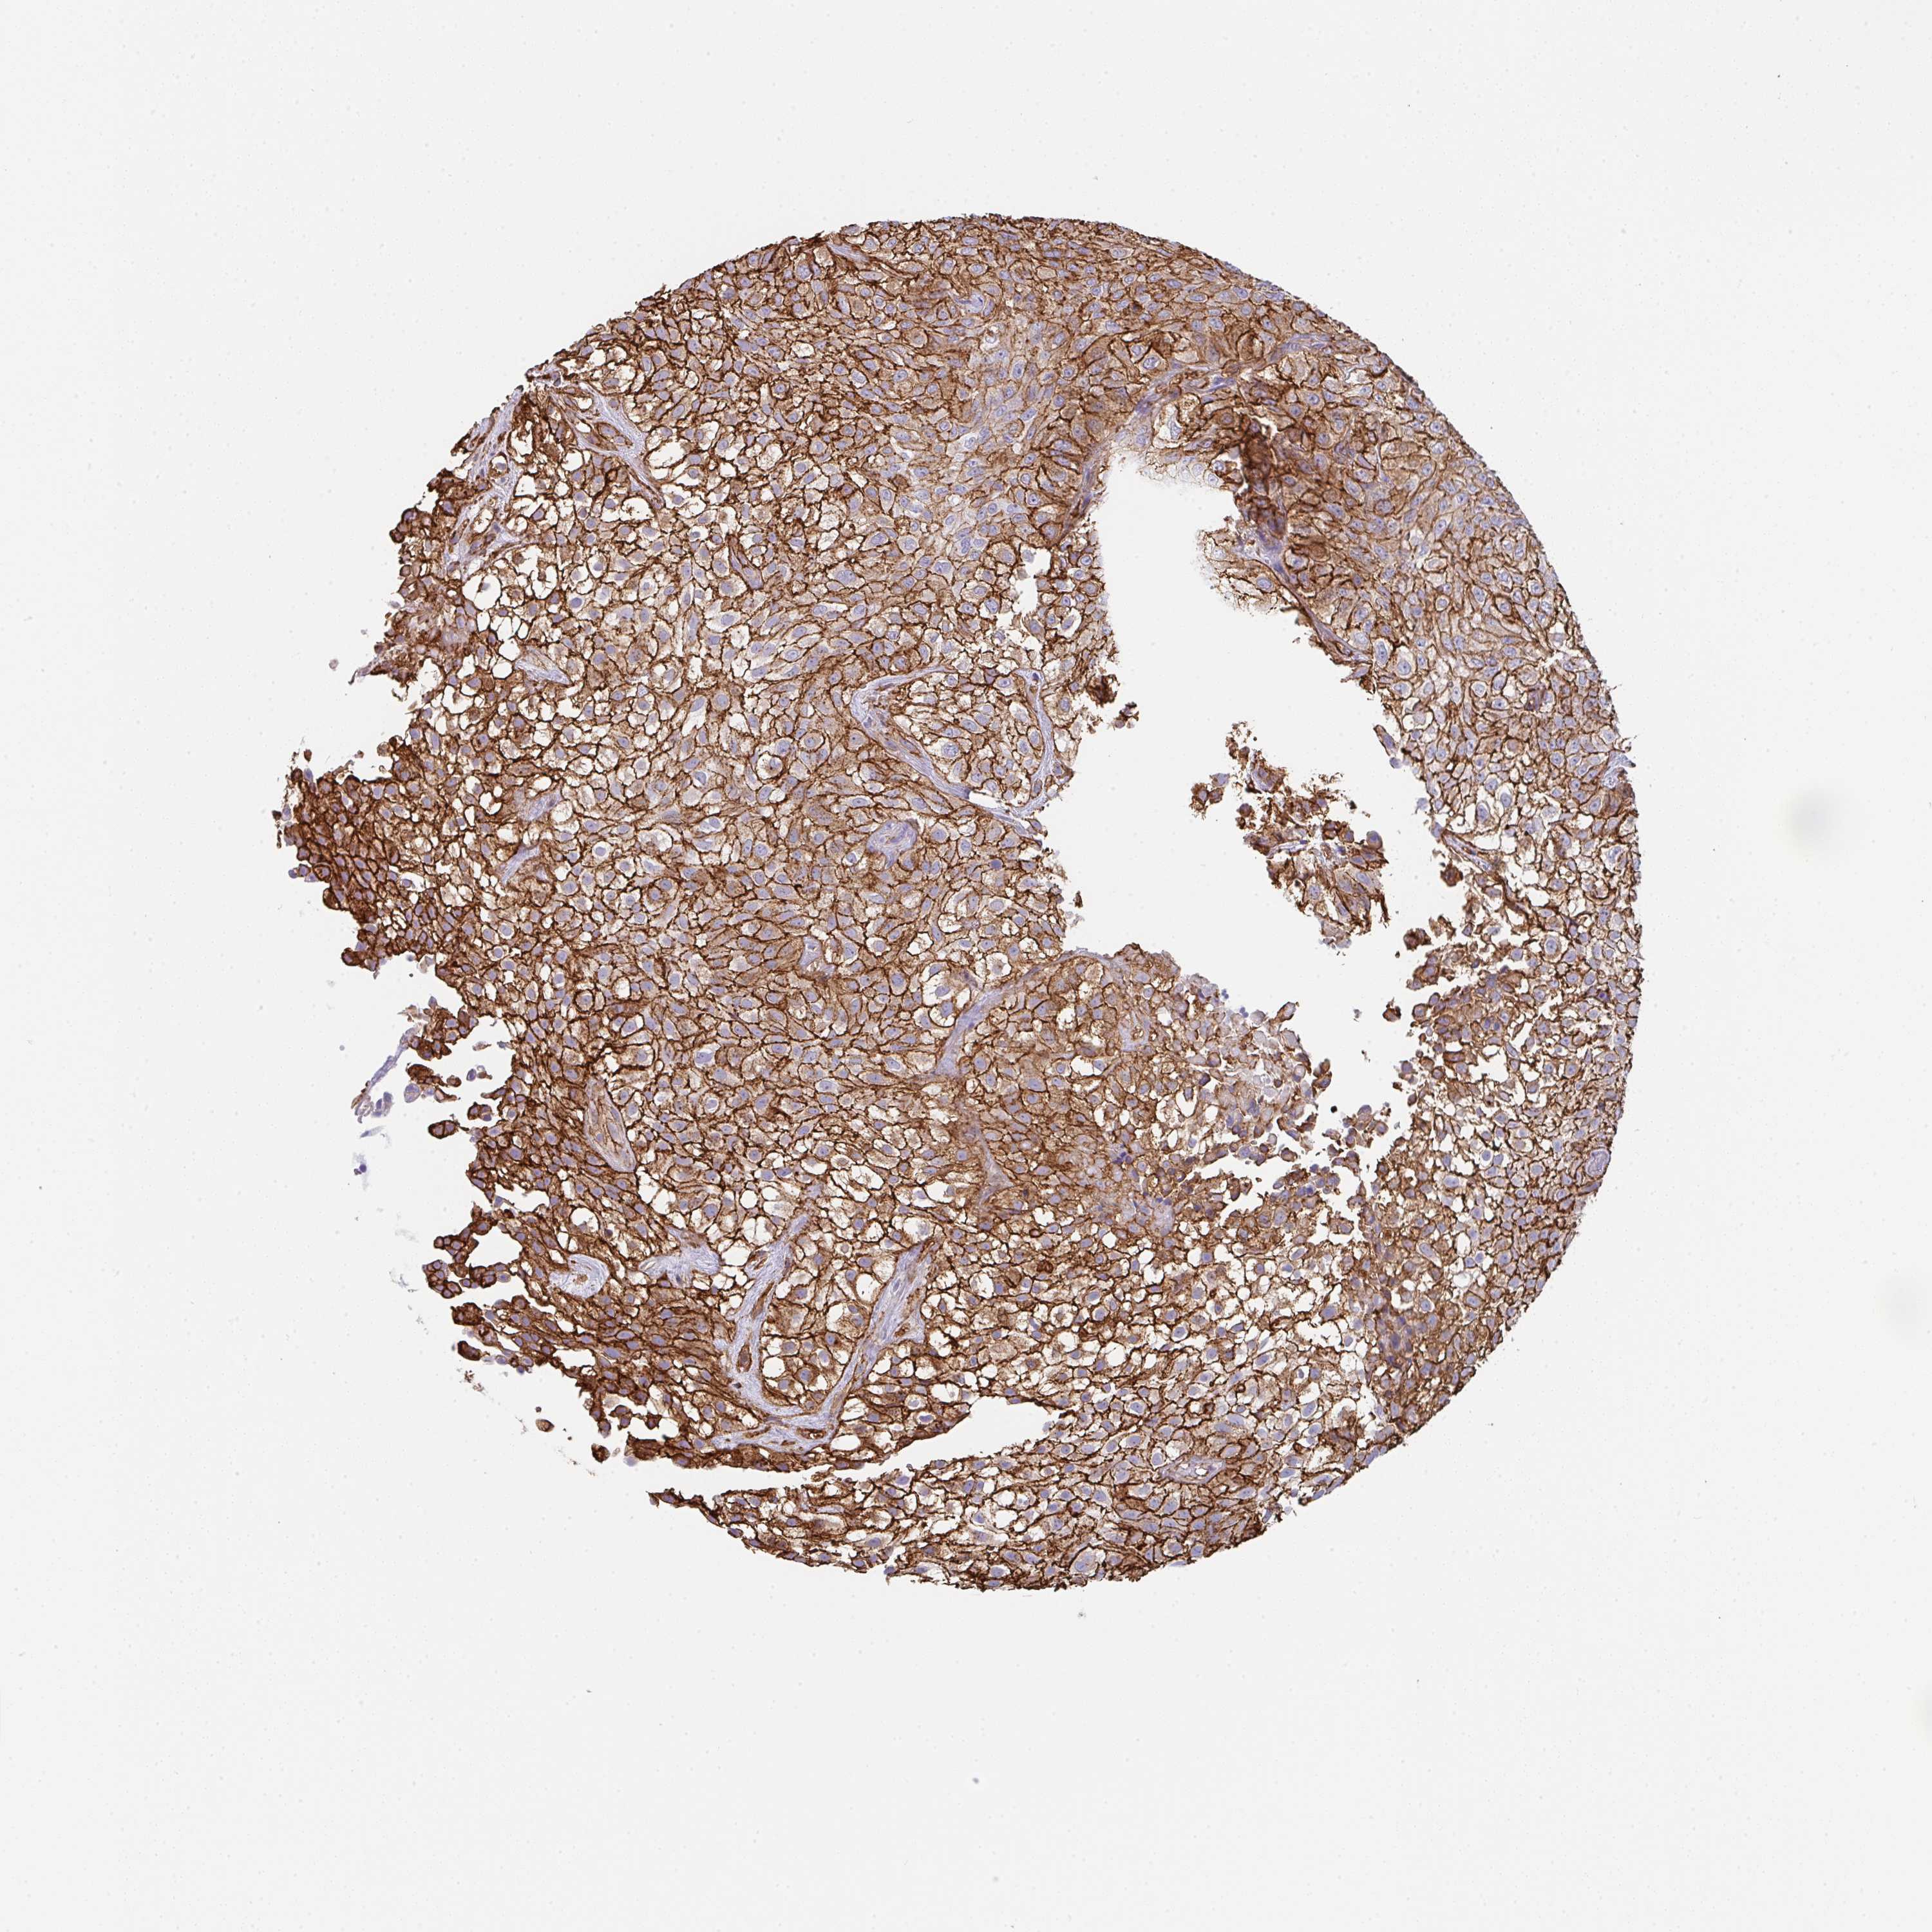

UROTHELIAL CANCER - Protein expressioni

A mouse-over function shows sample information and annotation data. Click on an image to view it in a full screen mode. Samples can be filtered based on level of antibody staining by selecting one or several of the following categories: high, medium, low and not detected. The assay and annotation is described here.

Note that samples used for immunohistochemistry by the Human Protein Atlas do not correspond to samples in the TCGA dataset.

Antibody stainingi

Antibody staining in the annotated cell types in the current human tissue is reported as not detected, low, medium, or high, based on conventional immunohistochemistry profiling in selected tissues. This score is based on the combination of the staining intensity and fraction of stained cells.

Each image is clickable and will lead to virtual microscopy that enables deeper exploration of all samples and also displays staining intensity scores, fraction scores and subcellular localization as well as patient and tissue information for each sample.

Antibody HPA051452

Antibody HPA056940

Urothelial carcinoma, High grade

Urothelial carcinoma, Low grade